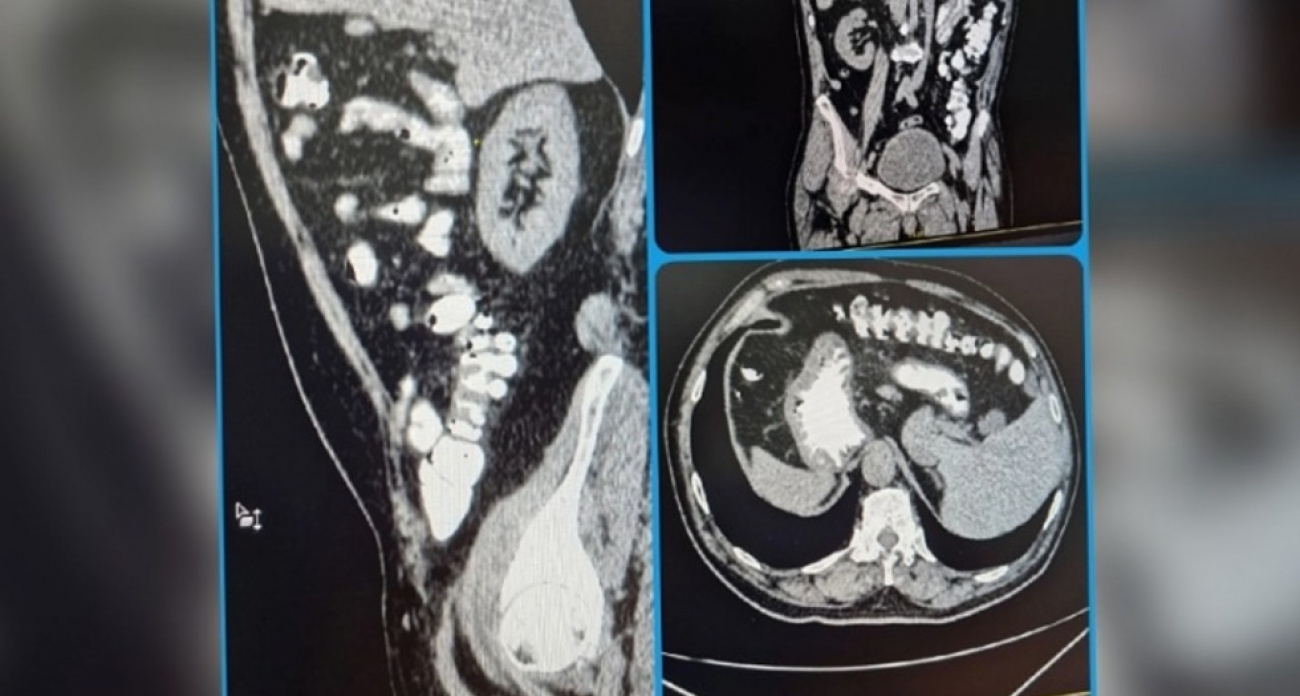

У жителя Саратовской области обнаружено редкое анатомическое явление - зеркальное расположение внутренних органов. Об этом необычном случае рассказали в Балаковской городской клинической больнице.

Данная особенность была выявлена случайно, во время компьютерной томографии брюшной полости и забрюшинного пространства.

Во время процедуры был выявлен вариант анатомической нормы, когда все органы пациента располагаются зеркально: печень - слева, сердце - справа, имеется зеркальное отображение аорты и лёгких. Подобная анатомическая аномалия встречается крайне редко и является признаком "случайной находки" при обследовании. Пациент не знал о наличии у него таких интересных изменений. Отмечена полная транспозиция органов. На самочувствии пациента это никак не отражается, ни на что не влияет.